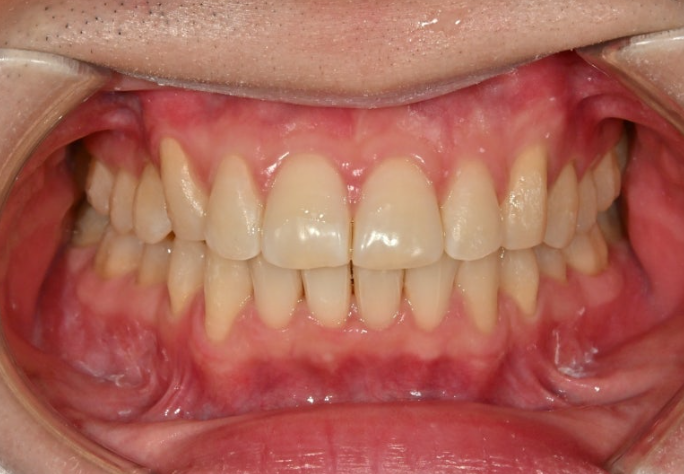

올해 초, 교정치료를 위해 내원한 30대 후반의 환자분입니다.

앞니가 깊게 물리는 과개교합.

중심선 불일치. 정도가 보입니다.

앞니가 많이 뻗쳐있습니다.

위 앞니 뻗침이 심하면 위 아래 앞니 사이 간극이 커지죠.

위아래 어금니 물리는 교합관계는 그래도 1급에 가깝습니다.

악궁모양이 약간 찌그러진 형태입니다.